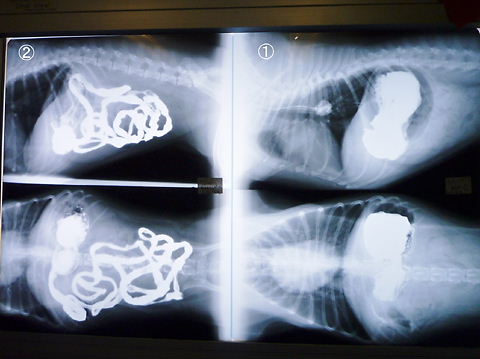

バリウム飲んでから、15分後・30分後・1時間後・・・と、

小まめに消化具合をレントゲンで撮ってくれたようで、全部は撮影しなかったけど

右が胃の中に入ってる図。左がその後腸へすすんでいく図。

さらに、左側図から右側図へとすすんで~この間・この後も何枚もレントゲンあり。

結局、見た感じでは何かが詰まってた(誤飲・腫瘍)感じは無く、いたって正常に

通過して行った様で…